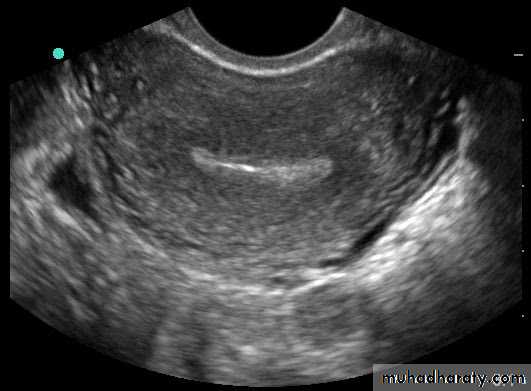

• Transvaginal US (TVUS): accurate assessment of gynecological problems and of early pregnancy up to about 12 weeks’ gestation